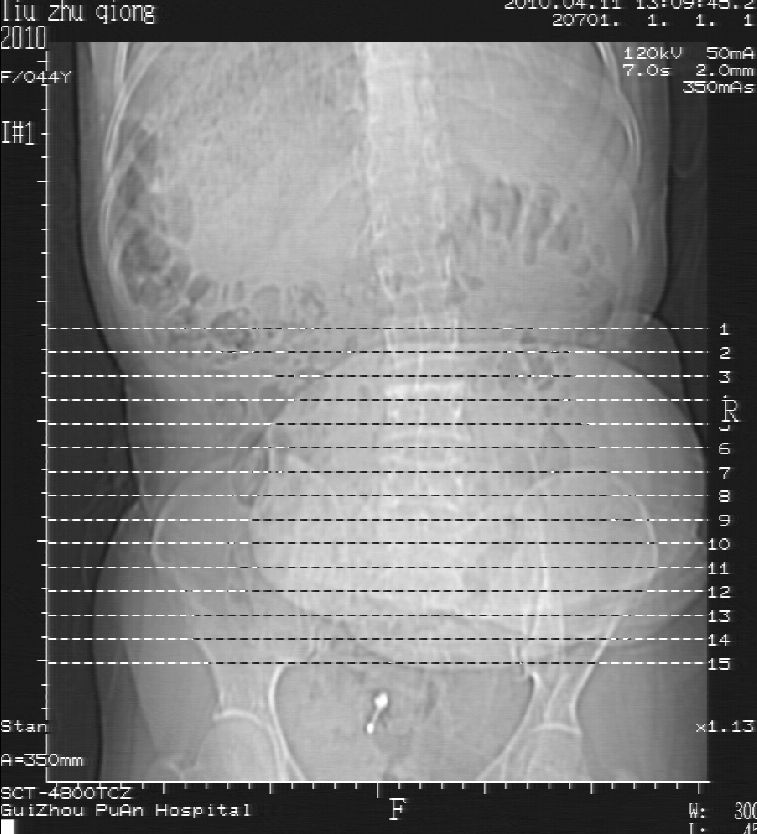

刘某,女,44岁,生第一胎时发现腰背部肿块,黄豆大小,至今17年,呈逐年增大,现行ct检查如下,敬请各位指点。

病史:女,44岁,腰背部肿块,黄豆大小,17年,呈逐年增大。

ct示:骶骨见软组织密度影,似见细条状,或花边状高密度影,考虑不典型钙化灶,向后生长,超出皮肤,可见骶骨破坏,第5幅ct图似与骶管相通。